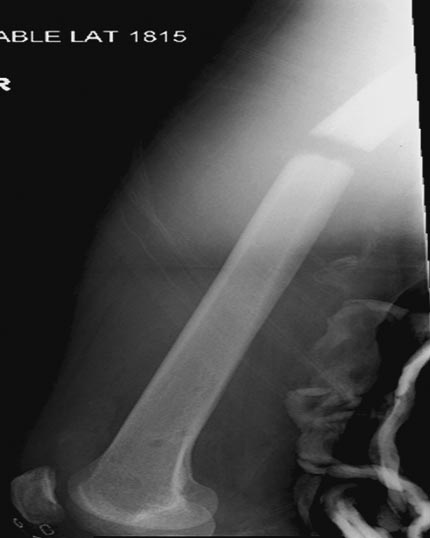

Здесь перечислены ортопедические повреждения: Rt. femoral shaft fracture, Rt femoral head fracture-dislocation, Rt distal femur fracture, Rt. open patella fracture, Rt. talus fracture dislocation, Rt. open humerus fracture, Left 5th metatarsal fracture, Left dislocation 1st TMT.

Интенсивные реанимационные мероприятия продолжаются в ICU, на следующий день сделана Irrigation &Debridement раны живота с последующим ушиванием серозной оболочки, наружный фиксатор на правое бедро. В связи со стабилизацией состояния получили добро на короткую операцию. Каккое из повреждении является более приоритетным? С чего начать?

Во время совместной операции с хирургами по I&D вакумированием раны живота и ран конечности, смогли быстро наложить наружный фиксатор на бедро.